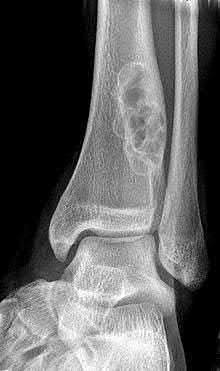

ORTHOPEDIC MCQS ONLINE 014 PATHOLOGY Musculoskeletal Tumors and Diseases Self-Assessment Examination AAOS 201…